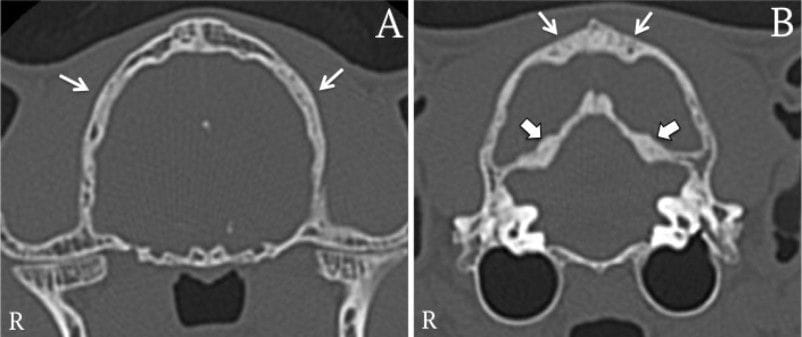

MRI revealed diffuse thickening and sclerosis of the calvarium, especially the occipital and temporal bones, with compression of the cerebellum and brainstem. The frontal lobes were reduced in size, the tentorium cerebelli was thickened, and mild ventriculomegaly was evident. CT confirmed generalized skull hyperostosis. Plasma retinol was markedly low at 0.1 µmol/L (reference 0.86–2.2 µmol/L), confirming hypovitaminosis A. Postmortem examination revealed diffuse skull hyperostosis causing frontal lobe compression and reduced cerebral volume. Histopathology demonstrated white matter spongiosis, Wallerian degeneration in the corona radiata and optic nerves, and meningeal thickening with mineralization. An incidental finding of systemic mastocytosis involving the spleen and liver was also noted.

A,B) Transverse CT images of the skull in a reconstructionwith a bone algorithm (window level: 450, window width: 4500).There is a generalised increased bone attenuation associated withhyperostosis affecting the temporal and occipital bones (small arrows;images (A) and (B), respectively) and tentorium cerebelli (thick arrowson image (B)).